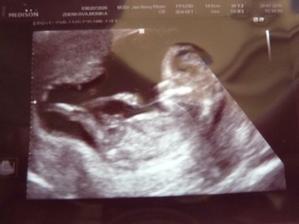

16.9.velký utz vše v pořádku mimčo měří 430g,poradna také v pořádku jen jsem dostala magnesium protože mi tvrdne břicho.Za měsíc mám 3 kg+